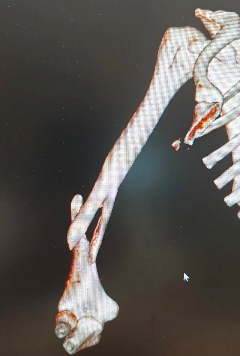

10月5日,40岁李先生摔倒致右肩部着地,8:40入院后,高峰医师团队诊断为“右肱骨近端粉碎性骨折”,13:35做好充分术前准备后历经3小时手术完成。